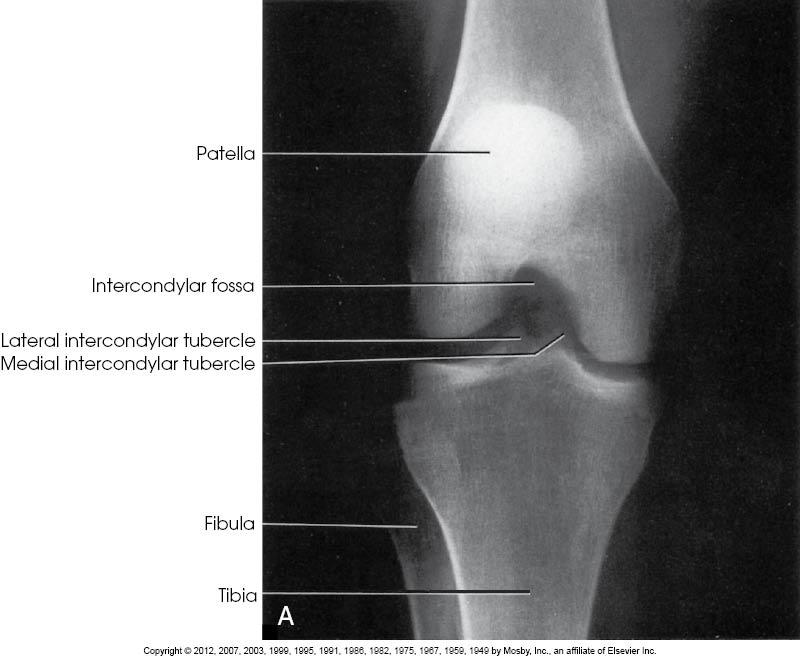

Structures Shown

• Open intercondylar fossa

•

Intercondyloid emminences

• Knee joint with soft tissue

PA Axial of the intercondyloid fossa, Camp-Coventry Method, Tunnel View